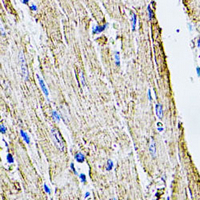

Immunohistochemical analysis of Filamin B staining in rat heart formalin fixed paraffin embedded tissue section. The section was pre-treated using heat mediated antigen retrieval with sodium citrate buffer (pH 6.0). The section was then incubated with the antibody at room temperature and detected using an HRP conjugated compact polymer system. DAB was used as the chromogen. The section was then counterstained with haematoxylin and mounted with DPX. -